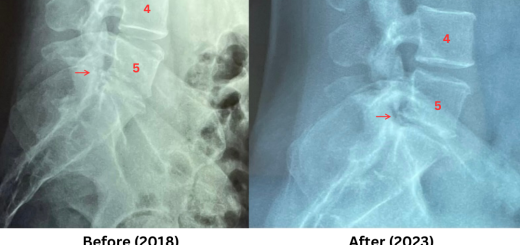

• Previous story Lumbar disc height

• Disc degeneration reversal